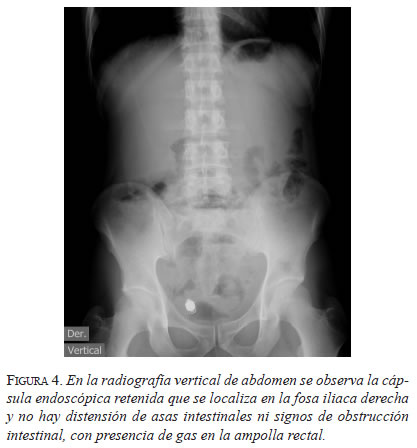

En la radiografía vertical de abdomen se observó la cápsula endoscópica retenida en la fosa ilíaca derecha, sin signos de obstrucción o distensión de asas intestinales, y con gas en la ampolla rectal (figura 4). Se practicó una TC de abdomen con contraste, donde se localizó la cápsula en la región del intestino delgado proximal.